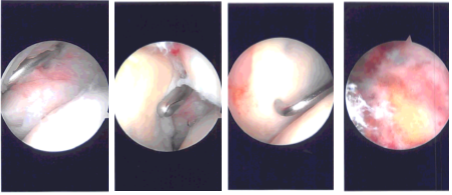

A shaver was introduced from the anterior portal and scoped from the posterior portal. Examination showed fraying of the glenoid labrum, partial tearing of the subscapularis, partial tearing of the biceps, and large rotator cuff tear. Tenotomy of the biceps was done intra-articularly and the tendon was allowed to retract.

Debridement of the glenohumeral joint of the labrum as well as subscapularis was performed using the shaver. Now, the arthroscope was entered into the subacromial space. Shaver was introduced from the anterosuperior portal and bursa was debrided. Acromial spur was seen.

A large rotator cuff was present. The landmark on the rotator cuff was prepared using a burr. After the bursectomy and preparation, repair of the rotator cuff was performed using Arthrex triple-loaded anchors. Two sutures with four tails of both anchors were used to pass mattress sutures.

The sutures were tied on each other, which allowed rotator cuff repair. The rotator cuff was initially mobilized with the use of shaver and wand. It was retracted up to the level of the glenoid and was difficult to get. After the knots were done, the rotator cuff was satisfactorily repaired.

A trial for lateral load was performed, but could not be done due to the swelling in the bursa. Now, the thermal wand was used to do the subacromial decompression followed by burr to excise the subacromial spur. Distal clavicle excision was also performed using the burr for the posterior as well as anterior portal sequentially. Final pictures were taken and saved.

Intraoperative Arthroscopy Images